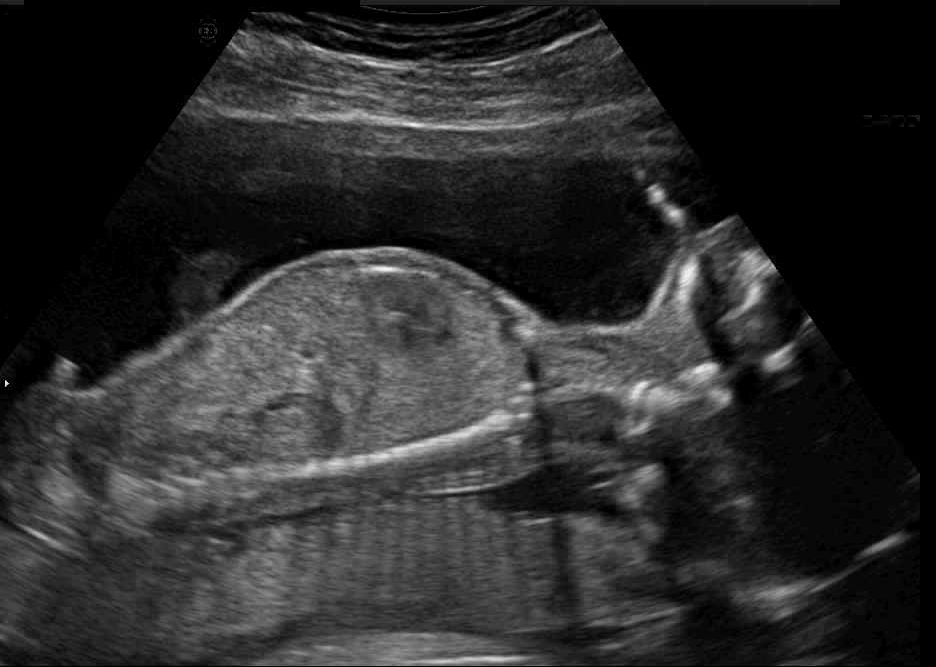

Real in-vivo images. 22 ultrasound sequences were collected using a GE Voluson E8 machine during standard fetal screening exams of 8 patients. Each sequence is several seconds long. We extracted all 4427 frames and resize them to , see Fig. 2 for some examples. The resulting image set was randomly split into training-validation-test sets by a 80-10-10% ratio.

Comparison to state-of-the-art. As seen qualitatively from the examples in Fig. 3, our method substantially outperforms the alternatives in terms of content preservation, while translating realistic US appearance. CycleGAN, SASAN, and CUT hallucinate inexistent tissue regions fail to generate fine anatomical structures, e.g. the ribs. StarGAN fails to generate faithful ultrasound speckle appearance, which leads to highly unrealistic images. Our method ConPres preserves anatomical structures, while enhancing the images with a realistic appearance. It further faithfully preserves acoustic shadows, even without explicit enforcement. However, as seen from the last column, the refraction artefact appears artificial in the images translated by all the methods. Note that although the imaging field-of-view (FoV) and probe opening in the simulation is significantly different from the real in-vivo images (Fig. 2) used for training, our ConPres maintains the input FoV closely compared to previous state-of-the-art. The results in Tab 2 quantitatively confirm the superiority of our method. Note that SSIM and FID/KID are used to measure translation performance from two different and sometimes competing aspects, with the former metric for quantifying structure preservation and the latter metrics for image realism.